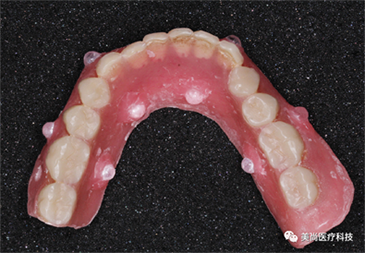

放射导板:

放射导板又称扫描义齿、放射义齿,是包涵了种植修复信息的带有放射标记点的活动义齿。它包涵了将来种植修复体的理想位置,使得医生在做术前设计时不仅考虑牙槽骨的情况,同时也考虑修复体的位置,以获得最佳的生物力学和美学效果。

安插多个放射阻射点(放射导板基托必须保证没有金属)

放入阻射物

• 阻射物必须突出基托表面0.5-1mm,去除干净周边粘接剂

• 用球钻在基托表面定位时,切勿穿透至组织面,切勿破坏组织面完整性

咬合稳定、就位准确、进行CT拍摄

放射导板展示图

放射导板